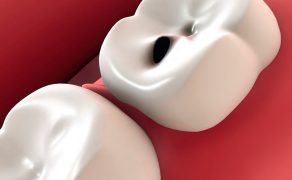

Szkolny program edukacyjny dla najmłodszych można podzielić na trzy etapy. Pierwszy składał się z omówienia budowy i funkcji zębów. Drugi to zabawy mające na celu przedstawienie zasad racjonalnego odżywiania. Trzeci etap to sprawdzenie wiadomości o szczotkowaniu zębów. Za każdym razem takim spotkaniom towarzyszył instruktaż na modelach stosowania szczotki elektrycznej i manualnej. Zajęcia realizowane były zgodnie z możliwościami wiekowymi dzieci.